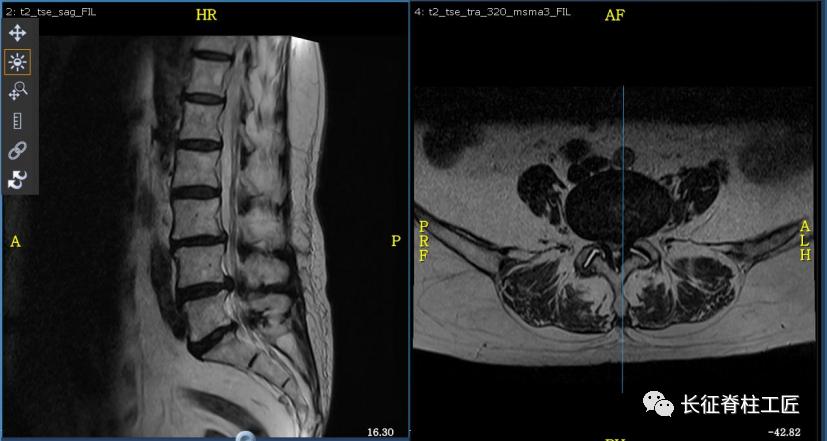

入院检查,腰部疼痛,后伸时加剧,局部压痛,双下肢肌力减退。X线检查,L4、L5骨质增生,MRI显示L4/L5、L5/S1椎间盘突出,马尾神经受压明显,被确诊为腰椎管狭窄症。

脊柱外科史国栋主任带领团队详细讨论,决定行椎管减压植骨融合内固定术。秉持微创的理念,术中通过精确的切口设计、肌肉组织的保护、手术时间的控制、后侧韧带复合体的保留等措施,在开放的手术中微创的完成了手术。